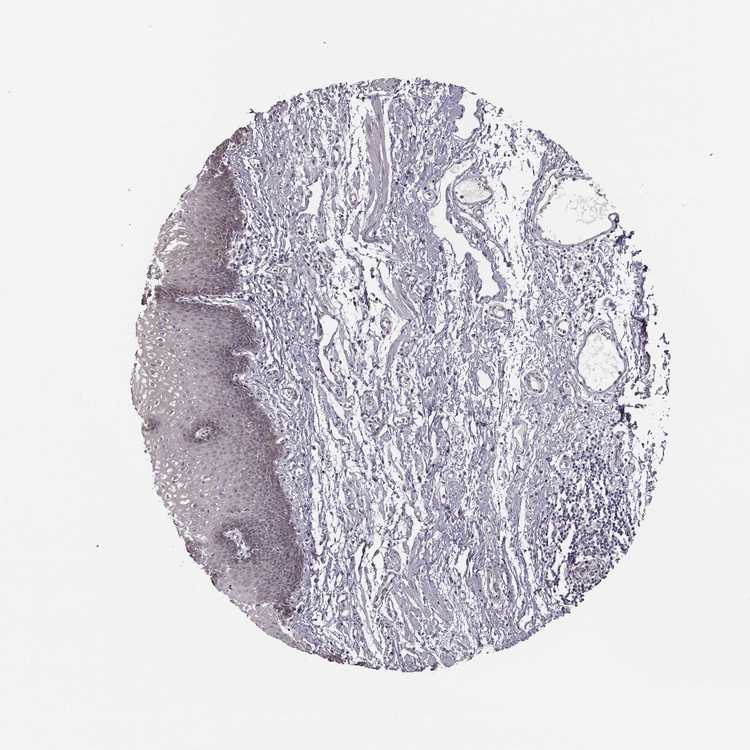

KAAG1